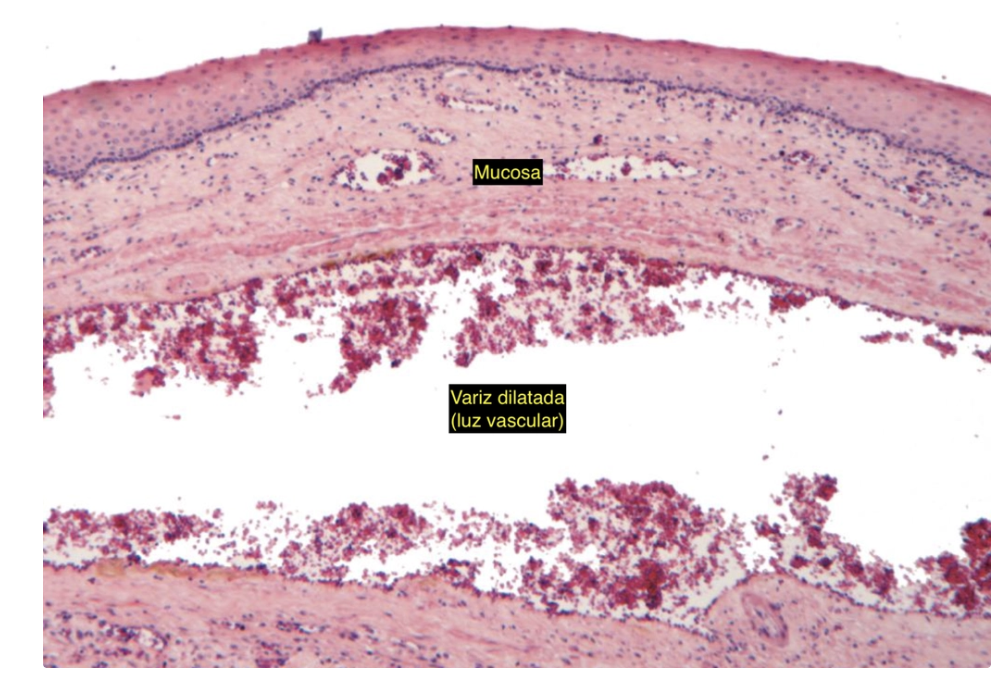

varices